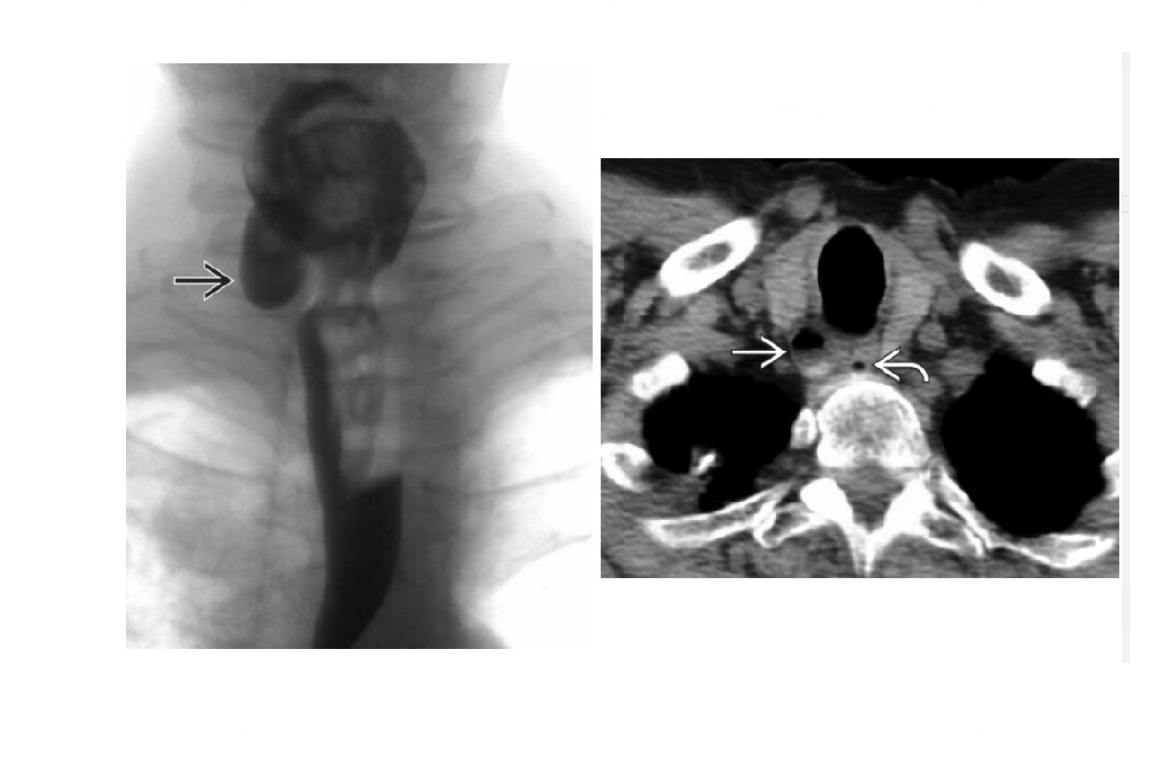

Zenker Diverticulum

Outpouching with rounded contour posteriorly in the neck is above the cricopharyngeus muscle

In hypopharynx!!!

Site of weakness is the Killian dehiscence - between the inferior pharyngeal constrictor muscle and cricopharyngeal muscle